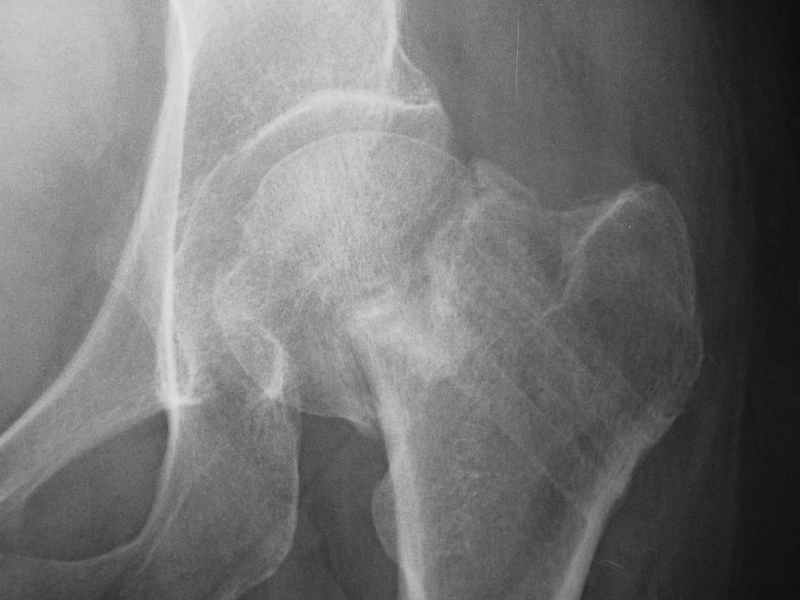

Нелеченный перелом шейки бедра / Neglected femoral neck #

Глубокоуважаемые коллеги,Вчера обратился мужчина 31 г. Травма 2 месяца назад, лечился в одном из городов области. Был не самый тяжелый перелом таза, который проведен консервативно. С ним и связывали невозможность поднять ногу.

Однако на сегодняшнем снимке обнаружился перелом шейки бедра. Больной уже ходитс частичной нагрузкой. Учитывая срок и картину на снимке, что предпринять? У нас предложены варианты 1)не оперировать, 2)закрыто 2 спонгиозных винта, 3)вальгизирующая остеотомия. Эндопротез как-то даже в список включать пока не хочется. Какие есть соображения? Что из перечисленного или что-то другое выбрать и почему? Заранее спасибо.

Dear colleagues,A male 31 years old treated elsewhere after not severe pelvic fracture, was managed non operatively. So the injury looked as a reason of his inability to elevate the leg. However at the recent x-rays the neck fractire was found. The patient already has been walking with partial weight-bearing.Looking at the x-rays and the time since the injury, what is the optimal treatment for now? We discussed 1)leave as is, 2)2 cancellows screws as is, 3)valgus osteotomy. Total hip replacement looks unnecessary yet.What is your opinion? Which option from the listed or something else should be preferred and why?THX in advance.

Варус тут за счет сдвига дистального отломка проксимально. Край шейки на периферическом отломке виден ведь хорошо.

Градусов на 25 больше.

При явно выраженном варусе и флексионных состояниях после сросшихся переломов шейки бедра у молодых рекомендуется реконструктивная операция по исправлению варуса для предотвращения раннего деформирующего артроза, приводящего в результате переднего импинжмента, как показано на снимке.